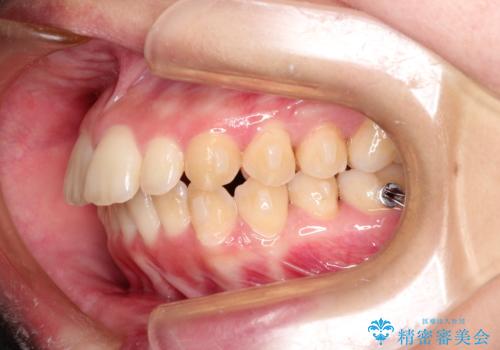

出ている前歯をインビザラインにて引っ込める

- 前歯が少し前に出ているのが気になるとのことで来院されました。

インビザラインにて上顎の歯を全体的に後方に移動させて前歯を引っ込める計画としました。

使用時間を守っていただけたので、比較的スムーズに矯正を終了することができました。